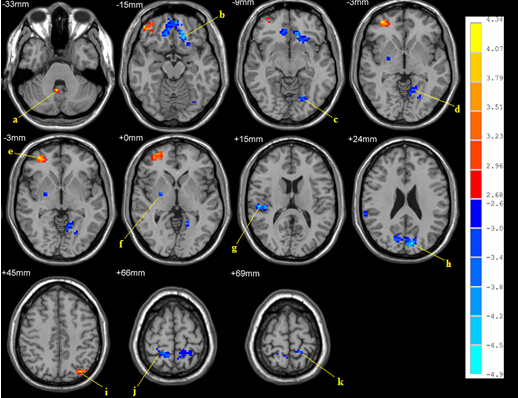

我们针对男性同性恋及男性异性恋者的静息态MRI数据进行了研究,发现:①男性同性恋组在静息态下ReHo显著增高的脑区有左直回、双侧中脑、左颞叶,ReHo显著下降的脑区有左枕下回、右枕中回、右枕上回、左楔叶和右楔前叶(图9)。男性同性恋组中ReHo与金赛量表评分显著正相关的脑区有左枕下回、左小脑、左中央前回、右中央后回,显著负相关的脑区有左运动上回和右顶上回(图10)。②采用低频振幅比例(fALFF)来比较男性同性恋与男性异性恋的静息态脑功能特征,发现:男性同性恋组静息态fALFF较强的脑区有右额中回、右小脑前叶,fALFF较弱的脑区有左中央后回、左舌回、右苍白球、右中央后回、左顶下回、右颞上回、左楔叶、左额下回(图11);左中央后回、左楔叶的fALFF与同性恋性取向呈正相关;而左枕下回、右颞下回、右小脑后叶的fALFF与同性恋性取向呈负相关(图12)。

图11. 男性同性恋与男性异性恋fALFF比较图(p < 0.01, corrected)。暖色和冷色分别表示男性同性恋对比男性异性恋fALFF增高和降低的脑区。指出的脑区分别为:(a)右小脑前叶;(b)左额下回;(c & d)左舌回;(e)右额中回;(f)右苍白球;(g)右颞上回;(h)左楔叶;(i)左顶下回;(j)右中央后回;(k)左中央后回